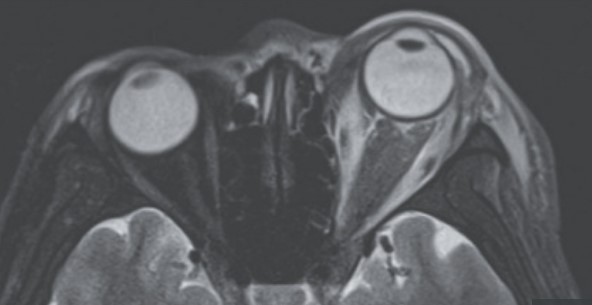

وأكد الأطباء أن الرجل التايواني فقد بصره بعد المعاناة لمدة 3 أيام من الألم الشديد والنزيف المستمر الذي نتج عن تمزيق مقلة عينه، وذلك عندما فحصوا عينه اليسرى التي تورمت بشدة، ووجدوا أنها لم تظهر أي حركة على الإطلاق.

وأضاف الأطباء أن تم تشخيص حالة هذا الرجل الأربعيني بشلل العين وعضلاتها، وأن الأوعية الدموية التي توجد أسفل السطح الشفاف للعين مباشرة مُصابة بالشلل بعد أن انفجرت بسبب الضغط الذي مارسته العين عليها، ما تسبب في تلف الأنسجة التي توجد حول العين، والنزيف الحاد.

وحسب ما نشر، أن الحالة تم تشخيصها بما يُطلق عليه طبيًا، الاعتلال العصبي البصري الإقفاري، واعتلال المشيمية، حيث إن الاعتلال العصبي البصري الإقفاري يحدث عندما لا يتدفق الدم بشكل صحيح إلى العصب البصري للعين، وهذا يمكن أن يؤدي في النهاية إلى تلف دائم لهذا العصب، المسؤول عن نقل الإشارات من العينين إلى المخ وتحويلها إلى صور يراها الفرد.

كما أن هذا الضرر الناتج عن اعتلال المخ الطبيعي، يؤدي إلى فقدان دائم للبصر، ولكن قد يظل بعض الأشخاص المصابين به يحافظون على بعض الرؤية المحيطية، نظرًا لما يتسبب فيه اعتلال المشيمية من تراكم السوائل تحت الشبكية، حيث الجزء الخلفي من العين الداخلية الذي يرسل معلومات الرؤية إلى المخ.